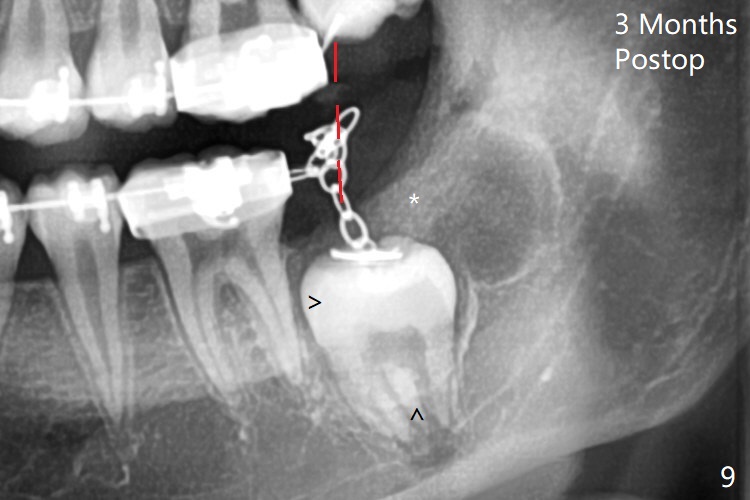

Treatment planning of surgical access to the impacted 7 (Fig.1) before CT analysis (to be canceled due to finance) include extraction of 8 (Fig.2) and removal of the bone coronal to 8 (Fig.3 red) so that there will be no bony block to 7 eruption (Fig.4). Place PRF or collagen plug in 8 socket to facilitate healing (Fig.3). Attach a retraction chain to the occlusal or buccal surface of 7 (Fig.6 pink) whenever it is convenient in term of hemorrhage and access (as mesial as possible). Remove 16 niti wires for brushing when the patient arrives. Cut 18 ss wire longer in the LL end (Fig.6 green to be bent to hook power chain (yellow)). Incision is shown as red in Fig.5. After 3 month delay, the thick buccal plate is removed from LL8 (1st) and 7 (2nd in sequence, as compared to Fig.2) to expose these unerupted teeth. In fact CT is not taken to decrease budget on the divorcing parents. A retraction chain is placed before extraction of LL8 with an intention to reduce hemorrhage (Fig.7). Although extraction requires several sectioning of the tooth, hemorrhage is mild to moderate. Instead of PRF and sticky bone (as compared to Fig.3), Osteogen plug is placed in the socket (Fig.8 OP). The bony septum between the 2 sockets is intentionally kept in place (*). 事实的确这样发生(图九:*)。埋伏牙不仅上移(^),而且远中移动(>),因为牵引方向(红虚线(橡皮筋),挂在上牙弓丝(图九:20ss:图十:18ss(之前))远端勾,积极牵引三个星期)。下次左上7放置舌侧纽扣,让病人更换橡皮筋。其实纽扣粘不住,上牙弓丝远中勾也不现实,只能使用橡皮筋挂在左上6,经常断。术后6个月,左下7继续上移(图十一)。这种低效率牵引仍然有效,牙齿继续上移,牙根长长(图十二:空箭头),但是受到左下6远中阻挡(*),所以下次在左上7咬合面装置舌侧纽扣和closed spring,改善牵拉方向(红箭头)。